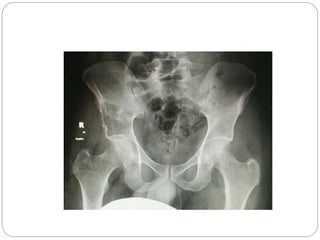

This document discusses 8 oncology cases. Case 1 involves a 40-year old female with right knee pain. Case 2 is a 28-year old male with a left subtrochantric fracture from a MVA who is now experiencing increasing left knee pain and swelling. Biopsy results showed high-grade osteosarcoma. Case 3 is a 30-year old female with breast cancer and bone metastases causing bilateral hip pain.